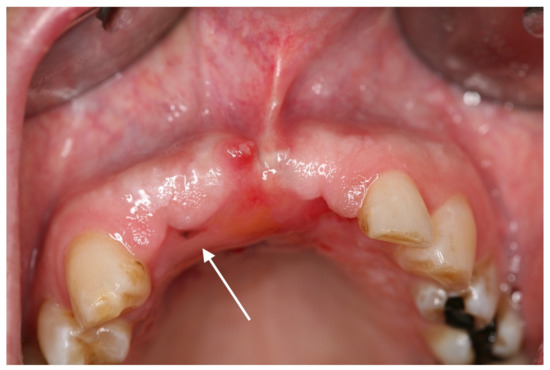

2. Case Report